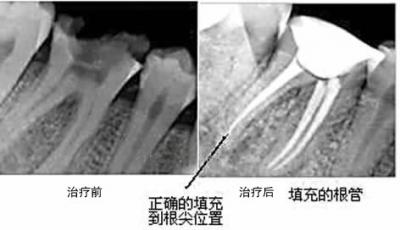

根管治療案例3

根管治療案例3